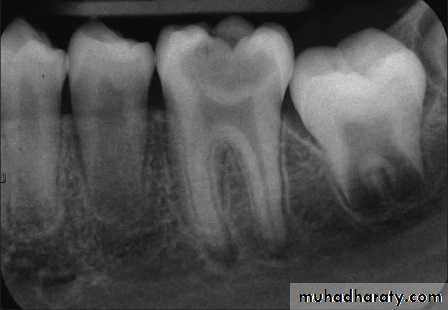

This is a clinical diagnosis based on subjective and objective findings indicating that the vital inflamed pulp is incapable of healing. The patient, however, does not complain of any symptoms. On occasion, deep caries will not produce any symptoms, even though clinically or radiographically the caries may extend well into the pulp.Left untreated, the tooth may become symptomatic or the pulp will become necrotic. In cases of asymptomatic irreversible pulpitis, endodontic treatment should be performed as soon as possible so that symptomatic irreversible pulpitis or necrosis does not develop and cause the patient severe pain and distress

Asymptomatic Irreversible Pulpitis

Symptomatic Irreversible Pulpitis